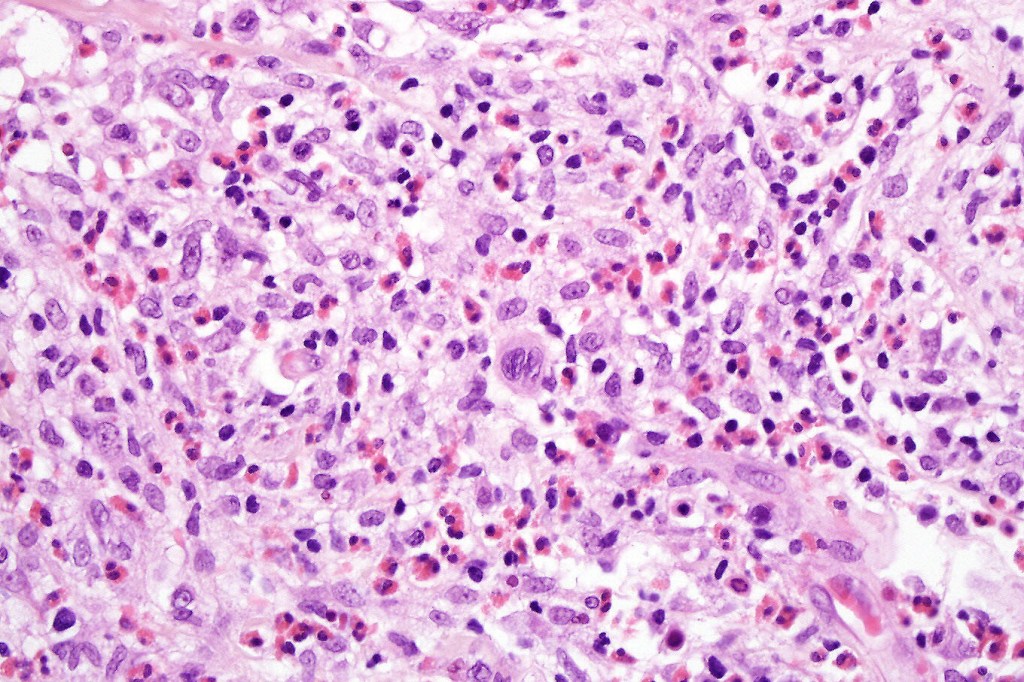

•Type A: 75-80%, wedge shaped infiltrate with base uppermost, large, anaplastic cells with abundant cytoplasm and vesicular nuclei containing prominent nucleoli, can resemble Reed-Sternberg cells, conspicuous mitoses & background infiltrate of lymphocytes, plasma cells, histiocytes, neutrophils & eosinophils